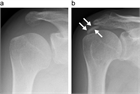

1. 急性の石灰沈着性滑液包炎は、腱板内に沈着した石灰が肩峰下滑液包へ流出して発生する結晶性滑液包炎である。突然発症する例が多い。

1. 腱板内に沈着した石灰が大きくなり、慢性化してインピンジメント症状や関節拘縮を引き起こすこともある。

1. 無症候性の石灰沈着症の発生率は人口の2.7~20%で、30~50歳に好発する。有症状の沈着症は50歳前後であり、女性(男女比は3:2)と棘上筋腱に多い。